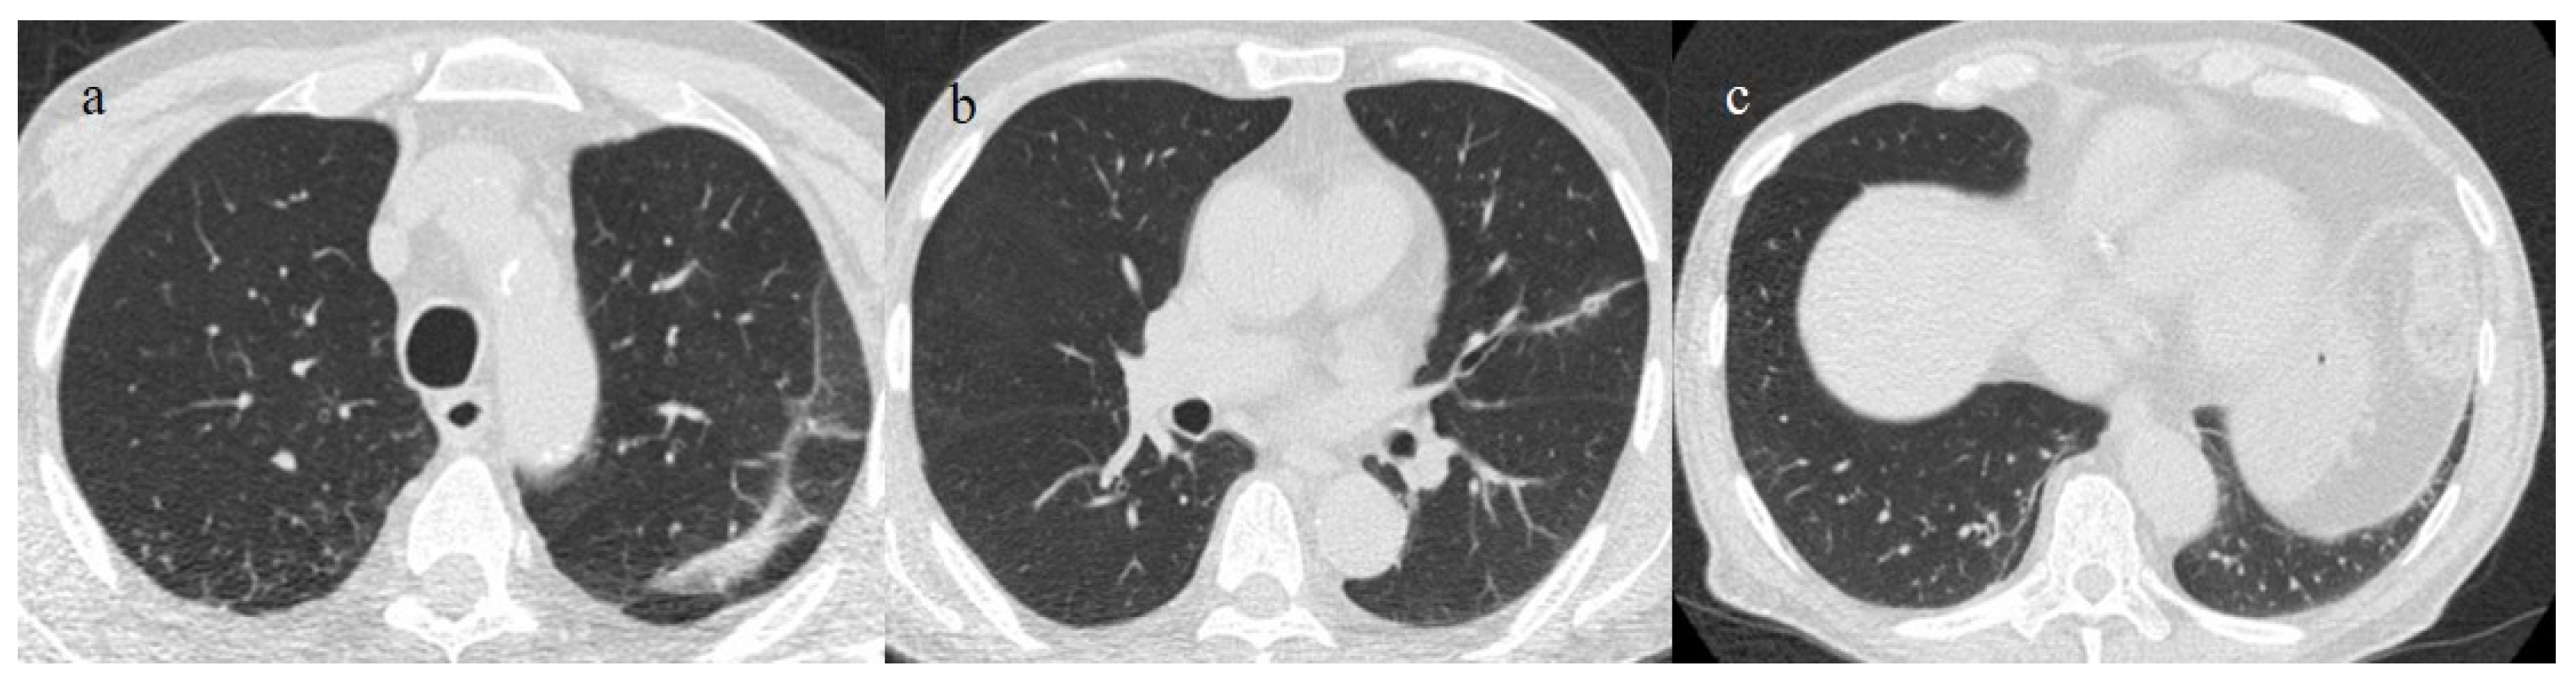

- Schultz, M.J.; van Meenen, D.M.; Bos, L.D. COVID-19-related acute respiratory distress syndrome: Lessons learned during the pandemic. Lancet Respir. Med. 2022, 10, 1108–1110. [Google Scholar] [CrossRef]

- Aslan, A.; Aslan, C.; Zolbanin, N.M.; Jafari, R. Acute respiratory distress syndrome in COVID-19: Possible mechanisms and therapeutic management. Pneumonia 2021, 13, 1–15. [Google Scholar] [CrossRef]

- Lu, S.; Huang, X.; Liu, R.; Lan, Y.; Lei, Y.; Zeng, F.; Tang, X.; He, H. Comparison of COVID-19 Induced Respiratory Failure and Typical ARDS: Similarities and Differences. Front. Med. 2022, 9, 829771. [Google Scholar] [CrossRef]

- Pfortmueller, C.A.; Spinetti, T.; Urman, R.D.; Luedi, M.M.; Schefold, J.C. COVID-19-associated acute respiratory distress syndrome (CARDS): Current knowledge on pathophysiology and ICU treatment—A narrative review. Best Pract. Res. Clin. Anaesthesiol. 2020, 35, 351–368. [Google Scholar] [CrossRef]

- Gosangi, B.; Rubinowitz, A.N.; Irugu, D.; Gange, C.; Bader, A.; Cortopassi, I. COVID-19 ARDS: A review of imaging features and overview of mechanical ventilation and its complications. Emerg. Radiol. 2022, 29, 23–34, Erratum in Emerg. Radiol. 2022, 29, 225. [Google Scholar] [CrossRef]